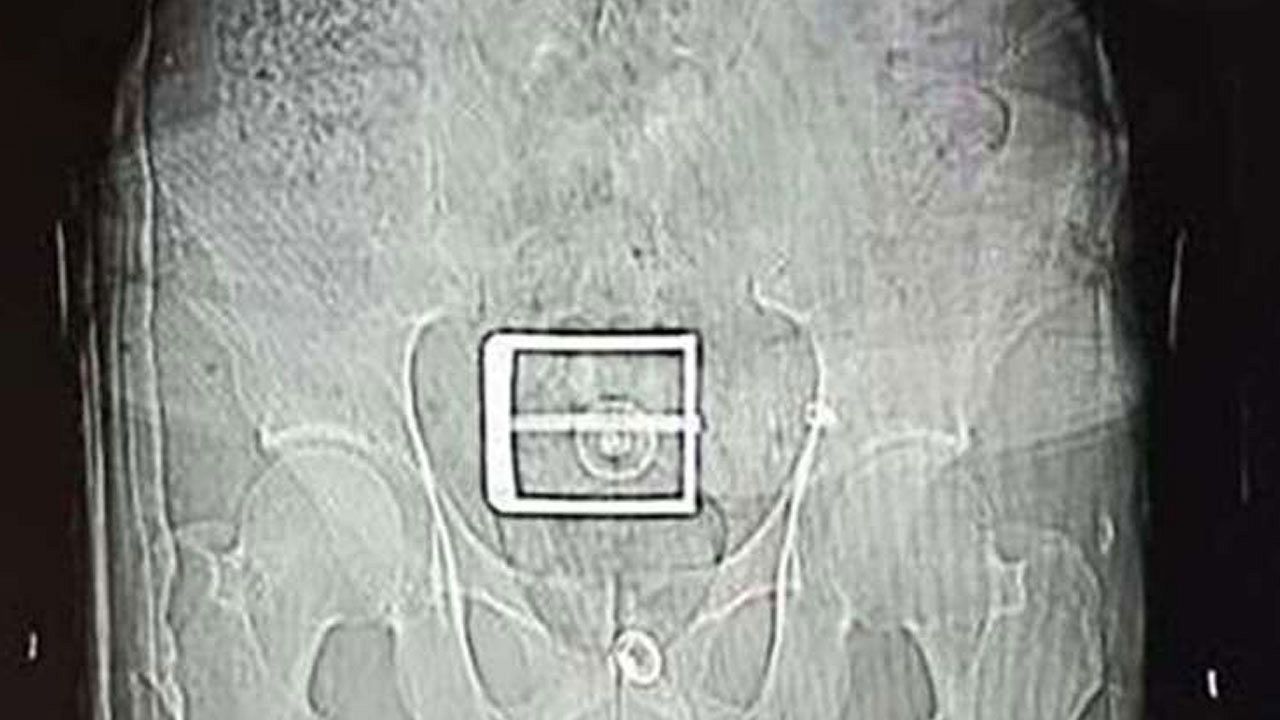

Şüphelinin, götürüldüğü hastanede çekilen mide ve bağırsak röntgen çekimlerinde, çok sayıda yabancı cisim tespit edildi.

Tıbbi müdahaleyle şüphelinin vücudundan 78 kapsül halinde 603,35 gram Afyon sakızı, 17 kapsül halinde 111,35 gram sentetik uyuşturucu çıkarıldı.